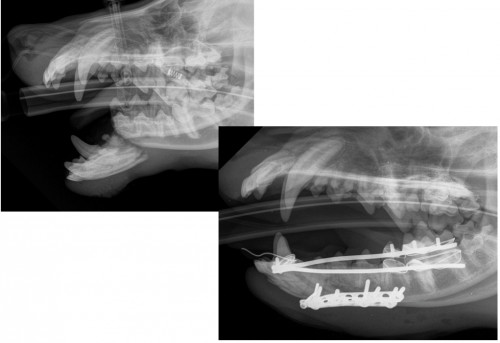

症例写真